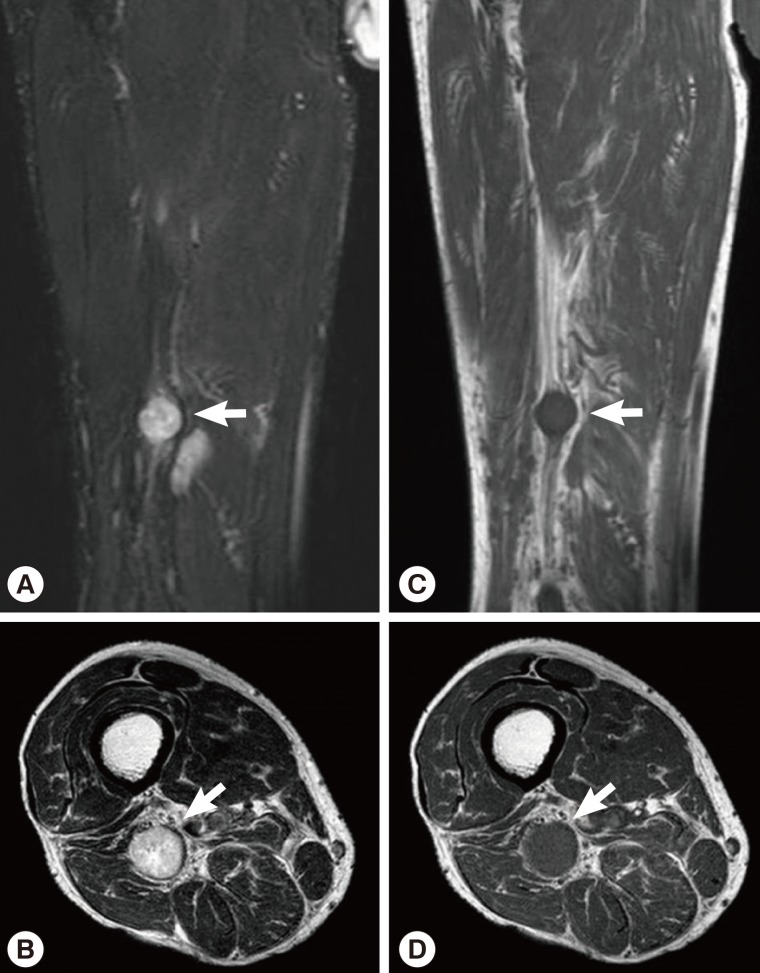

Routine laboratory test results were unremarkable, and no eosinophilia was noted. Plain radiographs of the right leg revealed multiple calcifications extending from the medial part of the knee to the calf. Ultrasonography revealed a heterogeneous, hyperechoic mass with a hypoechoic tubular lesion in the gastrocnemius muscle (Fig. 1), and MRI revealed multiple tubular and cystic lesions in the gastrocnemius muscle. The lesions showed high signal intensity on T2-weighted images and multilobulated, peripheral enhancing low signal intensity on T1-weighted images (Fig. 2). The patient was a farmer, and he had occasionally ingested raw snake meat when he was young. Preoperative serodiagnosis of human sparganosis by using a monoclonal antibody-based competitive ELISA was positive (3.79 in OD value) (negative < 1.00).

Currently, sparganosis can be diagnosed based on serology like ELISA. Sparganosis patients can often show eosinophilia [10]. Although the precise function of eosinophils is unclear, they are anyway involved in destroying the parasitic organisms [11]. A competitive ELISA that uses sparganum-specific monoclonal antibodies has been developed to improve the diagnostic specificity of sparganosis [12]. Even though our patient did not show definite eosinophilia, a monoclonal antibody-based competitive ELISA was positive. Radiologic evaluation, such as plain radiography, ultrasonography, or MRI, is also useful for the diagnosis of sparganosis. In our patient, preoperative ultrasonographic findings showed a heterogeneous, hyperechoic mass with a hypoechoic tubular lesion in the gastrocnemius muscle. This heterogeneous, hyperechoic mass is considered to be a granuloma that contains the living sparganum, and the internal hypoechoic tubular lesion is considered to be the empty migrating tract of the larva. Multiple calcifications seen on plain radiographs can also be considered the pathway along which the sparganum passed. In this case, we performed preoperative ultrasound-guided marking for suspected lesions. Therefore, we could easily find intramuscular sparganum during the surgery, although it is difficult to determine the location of the spargana with naked eyes in the operative field.

Fig. 1

Ultrasonography of the patient which revealed a heterogeneous, hyperechoic mass with a hypoechoic tubular lesion (crosses) in the gastrocnemius muscle.